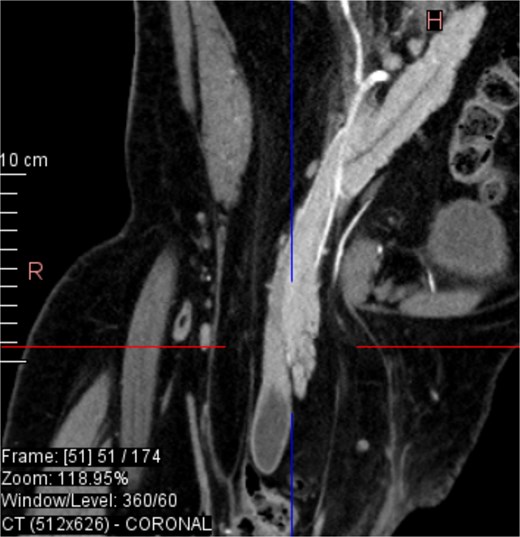

CT imaging (Figs 2–5) revealed a right inguinal hernia containing small bowel loops, ascending colon, the second and third portions of the duodenum, and the pancreatic head. The pancreatic head appeared rotated and displaced inferiorly into the hernia sac, without signs of acute pancreatitis.

Coronal CT view inguinal hernial sac with pancreatic head and D2 and D3 segment of duodenum.

Additionally, incidental findings (Fig. 2) included multiple calculi within the left hepatic duct. Though the patient was asymptomatic from a hepatobiliary standpoint, the presence of these stones raised concern for potential biliary stasis.